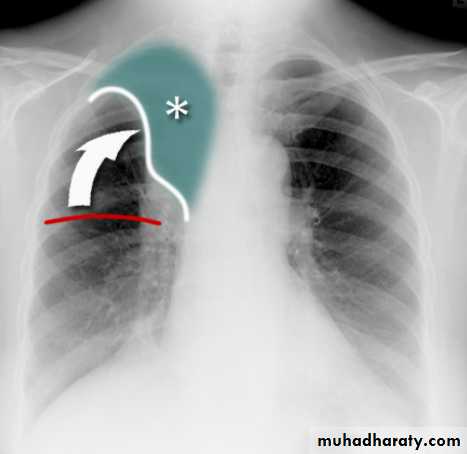

Right upper lobe collapse has distinctive features, and is usually easily identified on frontal chest radiographs .

Collapse of the right upper lobe is usually relatively easy to identify on frontal radiographs. Features consist of :

increased density in the upper medial aspect of the right hemithorax

elevation of the horizontal fissure

loss of the normal right medial cardiomediastinal contour

elevation of the right hilum

hyperinflation of the right middle and lower lobe result in increased translucency of the mid and lower parts of the right lung

right juxtaphrenic peak

A common cause of lobar collapse is a hilar mass. When a right hilar mass is combined with collapse of the right upper lobe, the result is an S shape to elevated horizontal fissure. This is known as Golden S sign .

Non-specific signs indicating right sided atelectasis are also usually present including:

elevation of the hemidiaphragm

crowding of the right sided ribs

shift of the mediastinum and trachea to the right